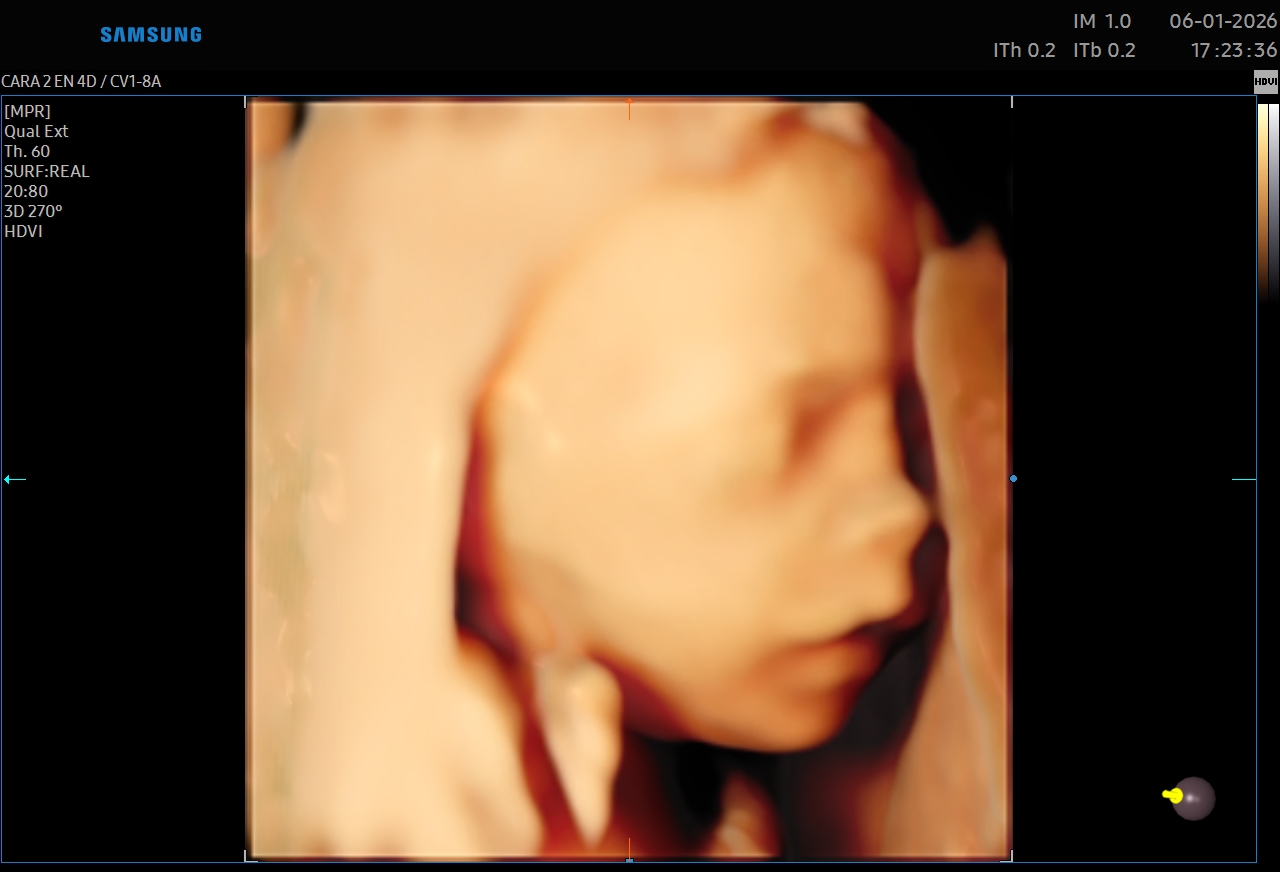

Ecografías 5D

La ecografía 5D es una experiencia única que te permite ver a tu bebé con un nivel de realismo sorprendente, capturando detalles como sus gestos, expresiones y movimientos en tiempo real.

Gracias a esta tecnología avanzada, podrás observar el rostro de tu bebé con mayor claridad, creando un vínculo emocional aún más especial antes de su nacimiento. Es el momento perfecto para compartir con tu familia y guardar recuerdos inolvidables de esta etapa tan importante.

Además de ser una experiencia hermosa, este estudio se realiza con equipos de alta tecnología y bajo supervisión médica, garantizando seguridad tanto para la mamá como para el bebé.